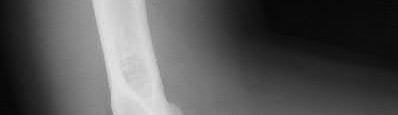

A 34-year-old male sustains the closed injury seen in Figure A as a result of a high-speed motor vehicle collision. What is the most appropriate next step in treatment?

The radiograph shows a comminuted pilon fracture, which is associated with high-energy trauma and significant soft tissue injury. The tested concept here is the importance of avoiding definitive reduction and fixation of this high-energy injury, which has been shown to be associated with an increased risk of wound complications and deep infections (as compared to staged treatment with usage of a spanning external fixator).

Patterson et al. reviewed 23 consecutive patients with comminuted distal tibia fractures. They showed 0% infections or wound-healing problems in their patient population treated with a two-staged protocol. Their protocol involved fibula fixation with an intramedullary implant and application of a medial external fixator to to regain length and restore anatomic alignment. Reevaluation of the limb occurred ten to fourteen days later for definitive fixation.

Sirkin et al. retrospectively reviewed 40 closed and 17 open pilon fractures (AO types 43A-C) that were treated with staged surgical management (avg. time from ext. fix. to formal reconstruction was 14 days (range 4 to 31) They reported 17% post-operative wound complication in the closed group and 11% post-operative wound complication in the open group (Gustilo Type I-III). They suggest the technique was successful in both closed and open pilon fractures.